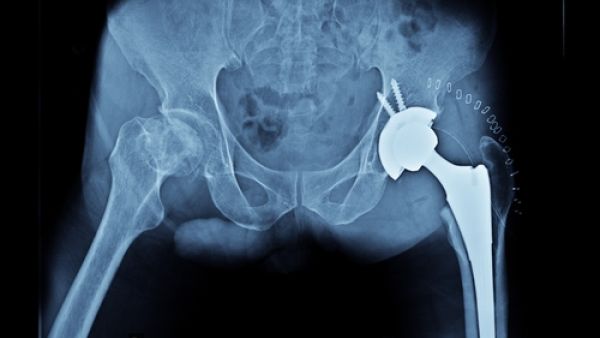

وأشارت الدراسة التي نشرت في دورية ماتوريتاس الطبيبة، إلى أن الرجال المتزوجين، كانت نسبة الإصابة لديهم بكسور الحوض أقل 50 في المئة ممن يعيشون بمفردهم، في حين بلغت النسبة 30 في المئة لدى النساء المتزوجات، أو اللواتي يعشن مع شخص آخر.

وقادت فريق البحث الطبيبة إلينا لوبو، من دائرة الطب الوقائي والصحة العامة في جامعة سرقسطة في إسبانيا. وحللت لوبو وفريقها، التاريخ الطبي والنفسي لأشخاص يتخطون 55 عامًا في سرقسطة، بلغ عددهم 4803 بينهم مَن عانى كسورًا في الحوض. وأشارت الدراسة إلى أن معدل الأعمــار في الدراسة 73 عامًا.

وبالنسبة إلى النساء في الدراسة، فإن الأمية زادت نسبة الكسور في الحوض حوالي 50 في المئة، كما زادها الاكتئاب بنحو 44 في المئة، في حين أن التدخين زاد النسبة لدى الرجال بمعدل الضعف ووصلت النسبة إلى ثلاثة أمثالها في حال وجود إعاقة.